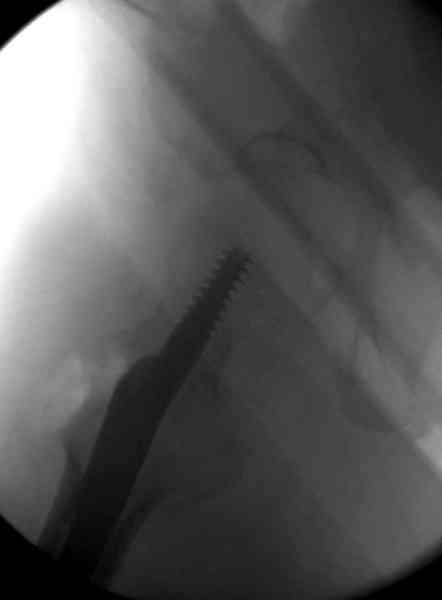

Изначально была выбрана не правильная точка введения стержня, в связи с чем в конце, я подчеркну, в конце операции произошло из-за напряжения между прокимальным концом канала бедра и стержнем разрушение в/3 бедра.

Проволока наложена потому, что при введении штифта не прошли эту зону римером и произошли сколы на концах отломков.

Под ЭОП во время операции такого смещения не было. Мы бы конечно не отпустили этого больного с такой картиной (сами бы что-то сделали или к вам отпр).